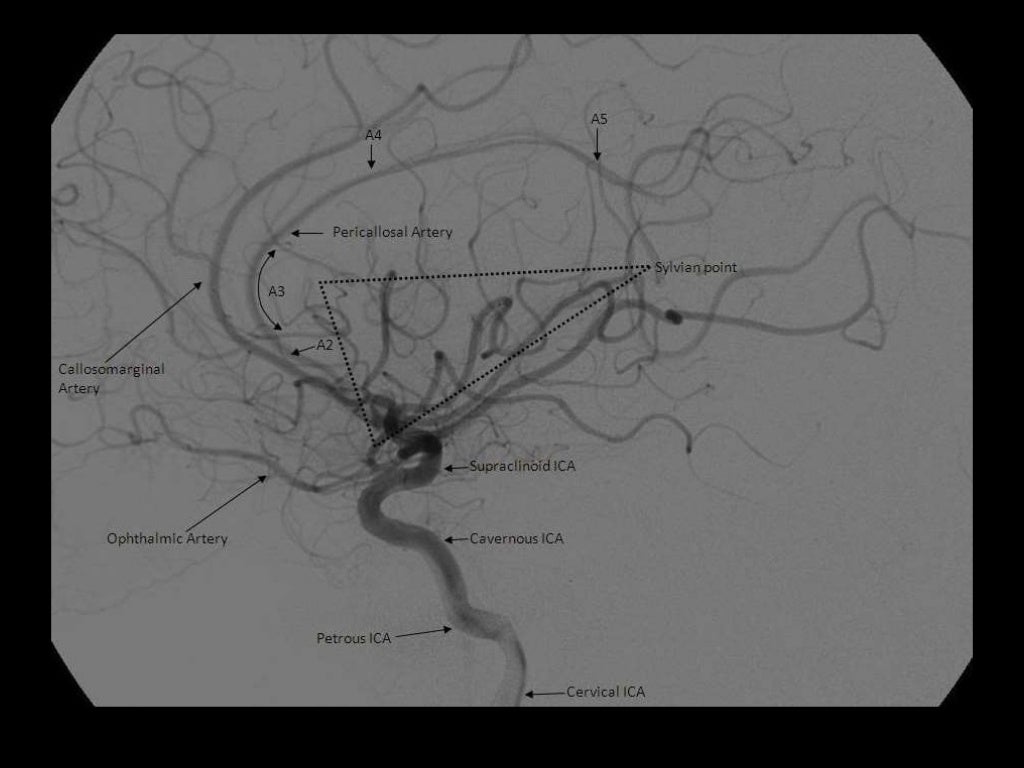

A1: ICA bifurcation to Acomm (horizontal)

A2: Acomm to origin of CMA around rostrum/genu junction (vertical)

A3: Genu to body of CC (proximal pericallosal)

A4/A5: Continuation of distal pericallosal (directly posterior)

NB angiographic sylvian point = apex of fissure sf. skull sylvian point a surface marking for fissure 3cm behind superior portion of zygomatic process

Callosomarginal A. (in cingulate sulcus)

Pericallosal A.